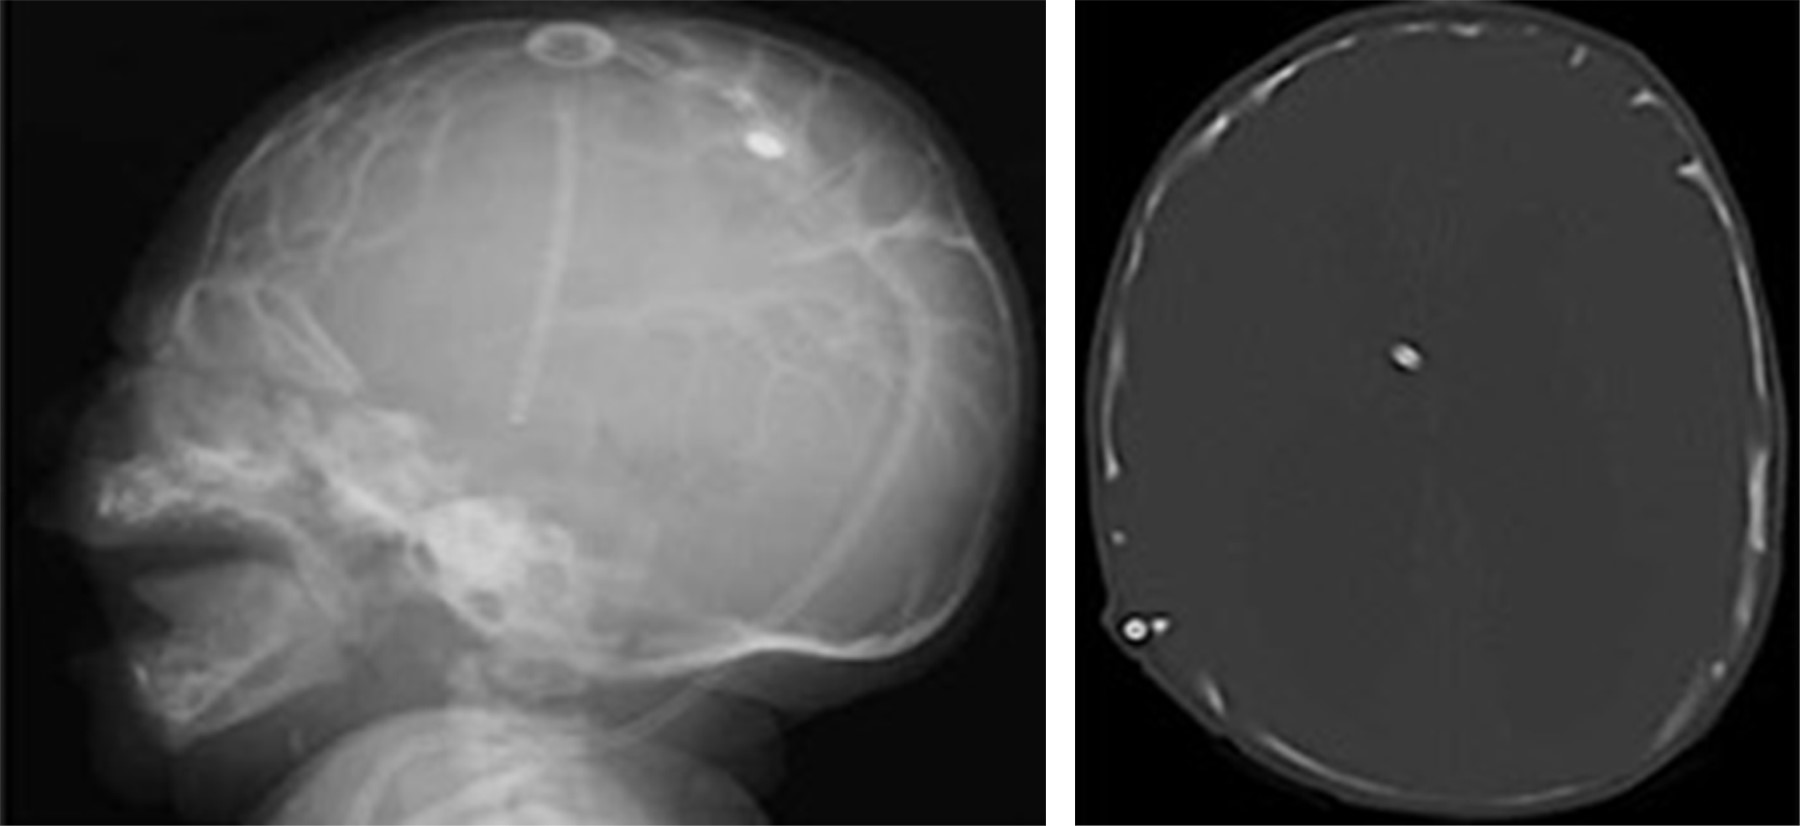

En la Figura 1 se muestran las radiografías de cráneo donde se observan múltiples imágenes radiolúcidas de tipo geográfico en todos los huesos de la bóveda craneal, con distribución simétrica, generalizada, delimitadas por imágenes lineales radiopacas bien definidas. Estos hallazgos radiográficos se consideran que, en conjunto, imitan la distribución y aspecto del patrón de giros y circunvoluciones cerebrales.

En la infancia, la presencia de enfermedades que afectan las suturas y fontanelas puede llevar a distintas alteraciones en la forma y tamaño del cráneo, así como diversas manifestaciones clínicas, como la hipertensión intracraneal.3-5 Pero el "cráneo en cobre batido o martillado" (aunque también se utilizan como sinónimos a latón martillado, plata golpeada o bronce martillado) se considera como una variante anatómica normal; el nombre hace alusión al aspecto observado en radiografía convencional y tomografía de impresiones de las circunvoluciones y de los surcos del encéfalo en la tabla interna del cráneo (Figura 3).5 Este signo radiológico ha sido descrito entre el primer año de vida y hasta los 13 años, y se cree que es una manifestación radiológica resultado de un crecimiento rápido del cerebro.6,7

Figura 3